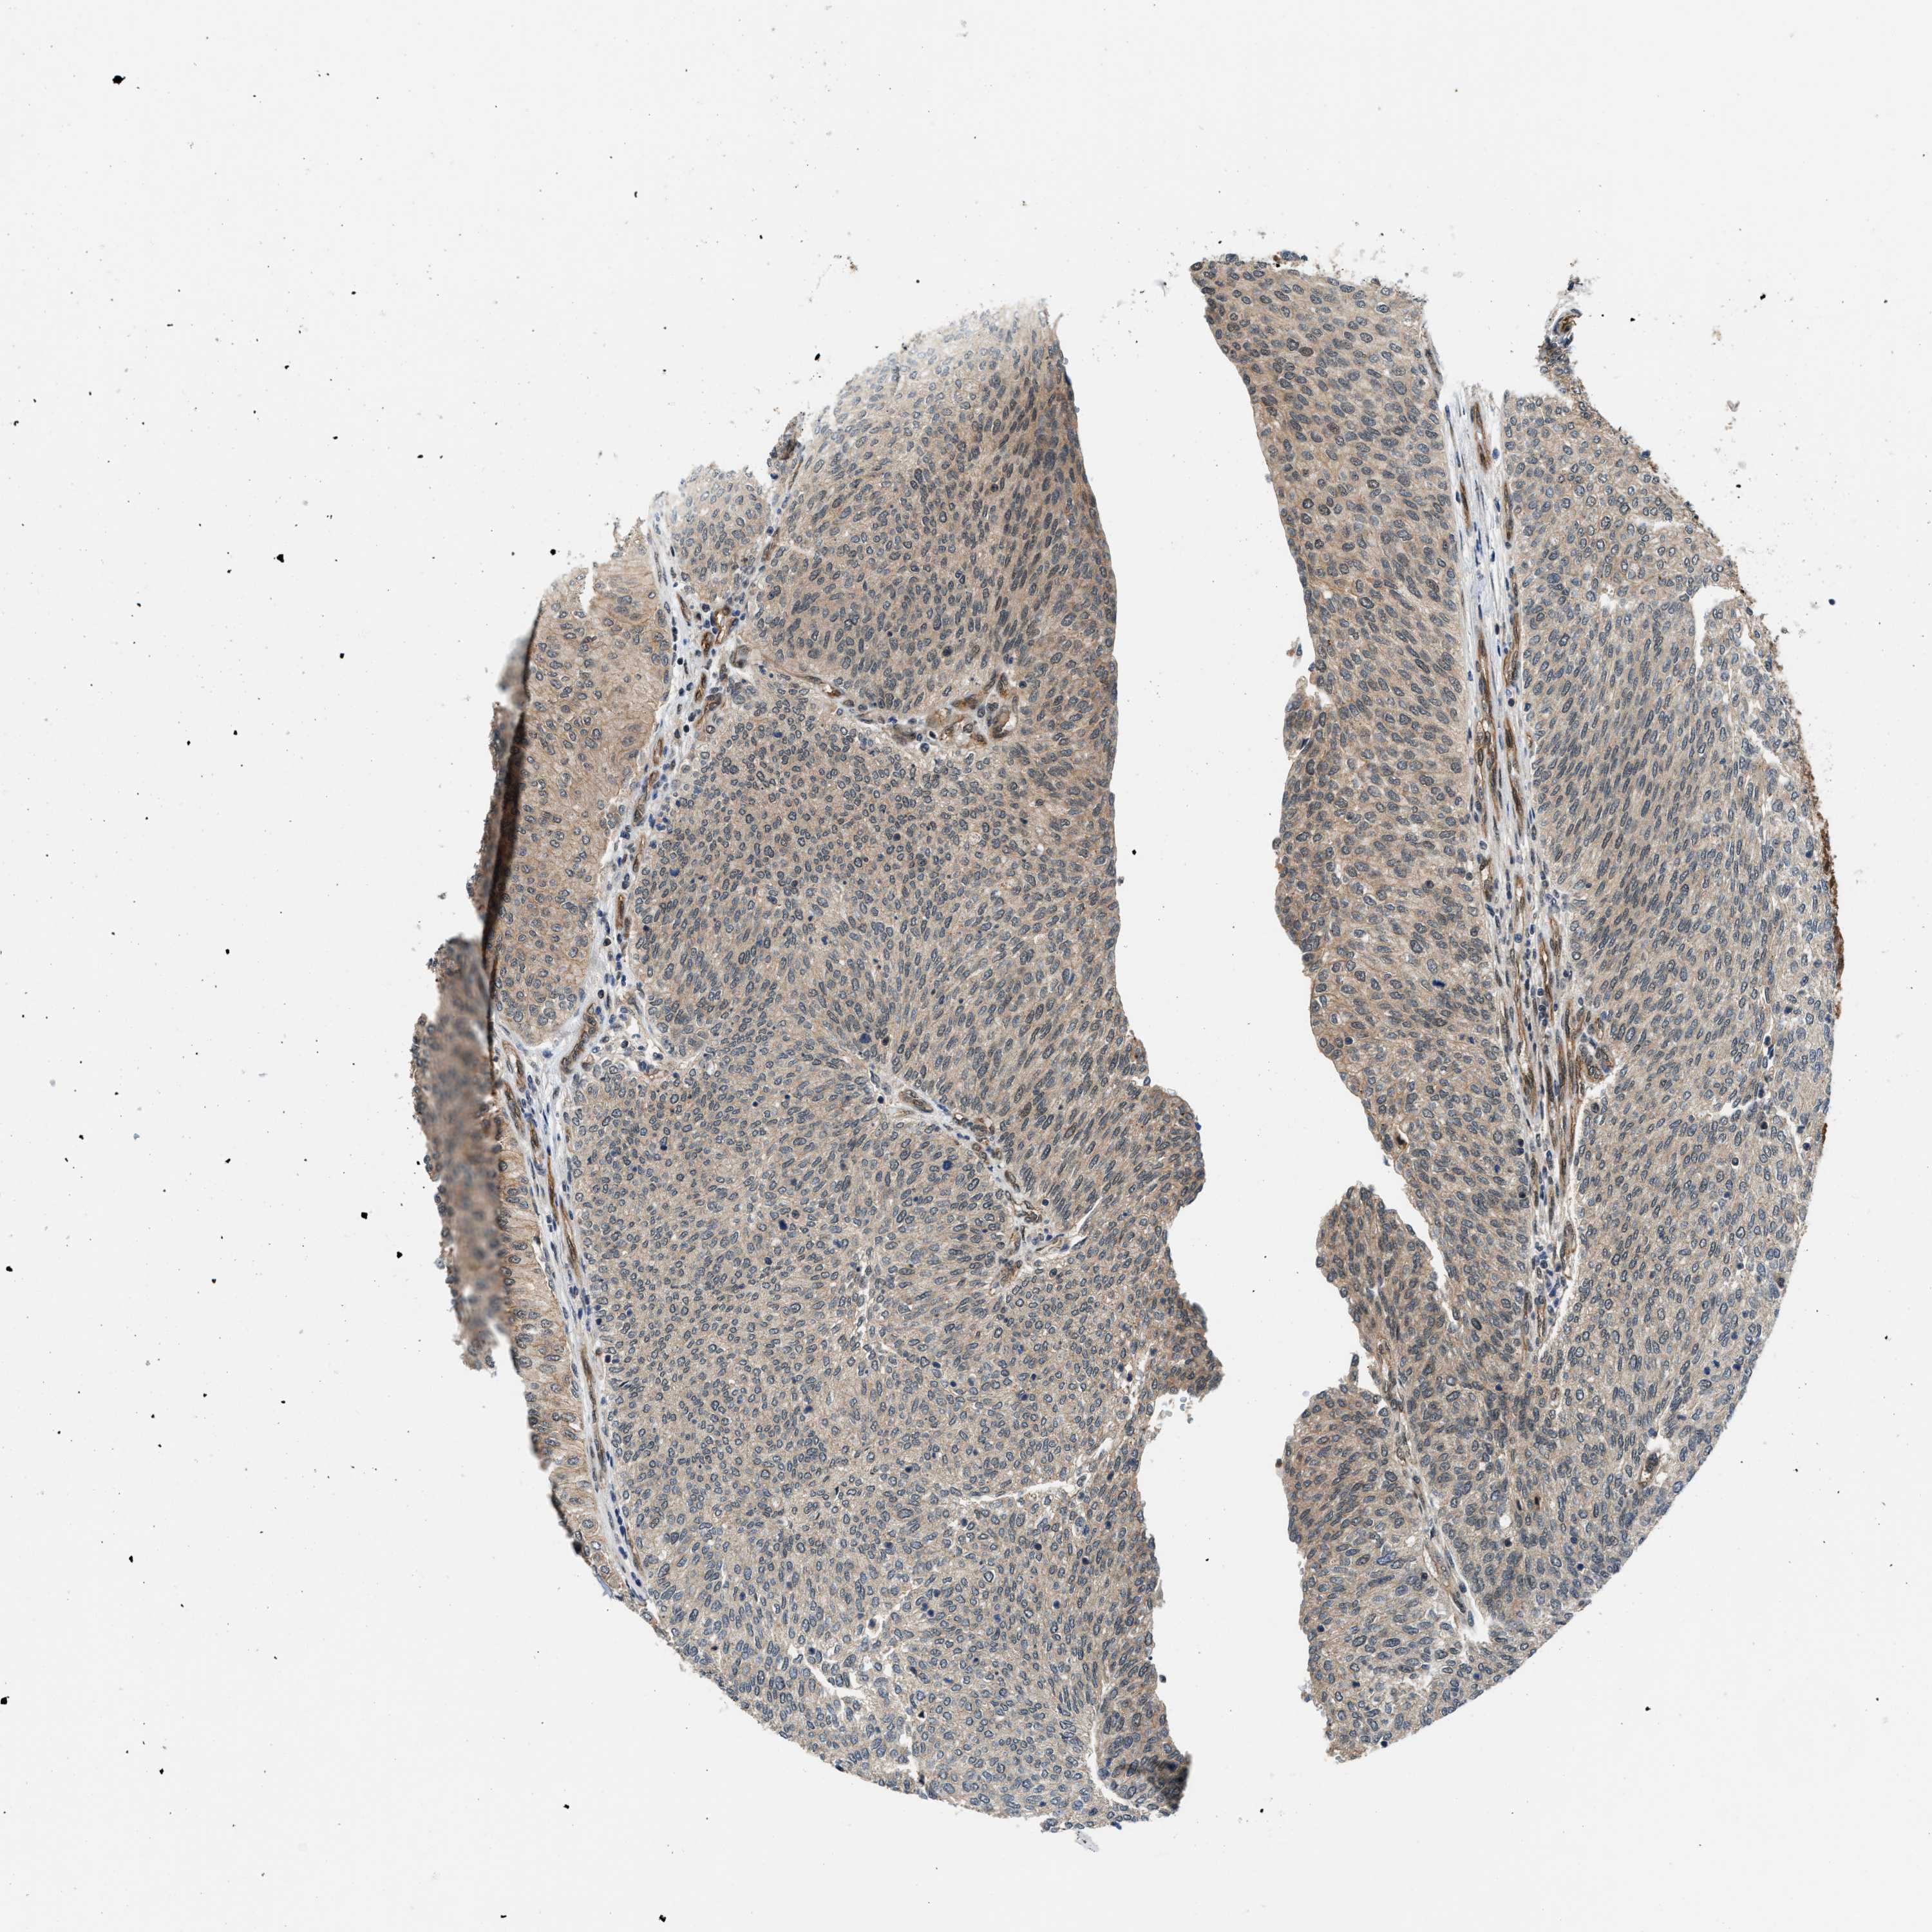

UROTHELIAL CANCER - Protein expressioni

A mouse-over function shows sample information and annotation data. Click on an image to view it in a full screen mode. Samples can be filtered based on level of antibody staining by selecting one or several of the following categories: high, medium, low and not detected. The assay and annotation is described here.

Note that samples used for immunohistochemistry by the Human Protein Atlas do not correspond to samples in the TCGA dataset.

Antibody stainingi

Antibody staining in the annotated cell types in the current human tissue is reported as not detected, low, medium, or high, based on conventional immunohistochemistry profiling in selected tissues. This score is based on the combination of the staining intensity and fraction of stained cells.

Each image is clickable and will lead to virtual microscopy that enables deeper exploration of all samples and also displays staining intensity scores, fraction scores and subcellular localization as well as patient and tissue information for each sample.

Antibody HPA016867

Antibody HPA018271

Urothelial carcinoma, Low grade

Urothelial carcinoma, High grade